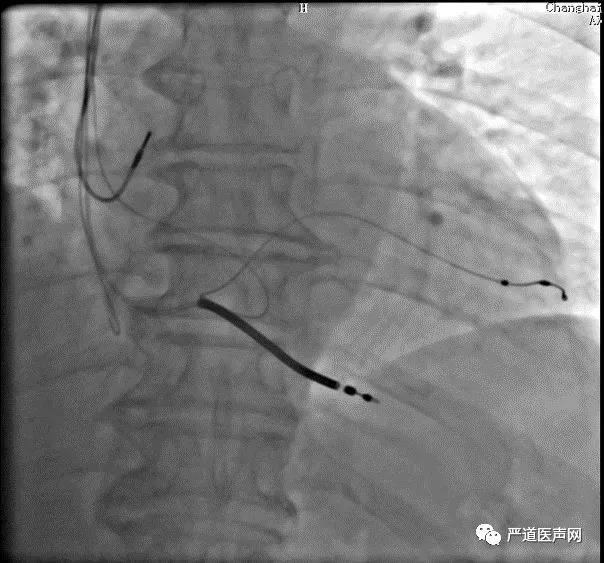

Swing技术的应用

•Swing技术:利用患者自身的心脏跳动,顶住四极导线电极,电极会逐步缓慢前行至靶静脉远端。

要点:

•避免过度用力,持续给力

•稳住导丝,透视下操作

电极最终定位

•LAO45°位

•AP位